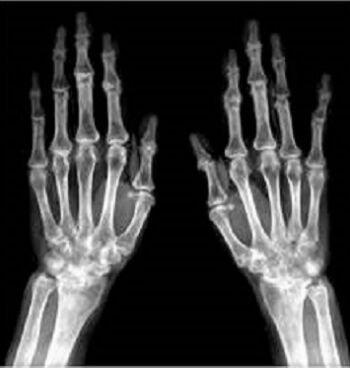

74.57歲女性雙手多處關節腫痛,雙手X光檢查如附圖,最可能的診斷為何? (A)gouty arthritis (B)osteoarthritis (C)septic arthritis (D)rheumatoid arthritis